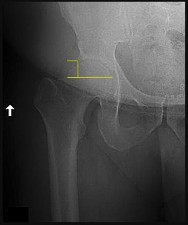

Prophylactic pinning of the contralateral hip in SCFE is controversial but is strongly indicated in patients with underlying endocrinopathies (e.g., hypothyroidism, growth hormone deficiency) or renal osteodystrophy. These conditions dramatically increase the risk of bilateral involvement. Other indications include inability to follow up, radiation therapy, and open triradiate cartilage (though age and triradiate status are debated, endocrinopathy is universally agreed upon).